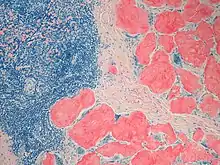

| Example of amyloid deposits under Congo Red staining |

LECT2 amyloidosis is diagnosed by a kidney biopsy which reveals two key findings: a) histological evidence of Congo red staining material deposited in the interstitial, mesangial, glomerular, and/or vascular areas of the kidney and b) the identification of these deposits as containing mainly LECT2 as identified by proteomics methodologies. Kidney biopsy shows the presence of LECT2-based amyloid predominantly in the renal cortex interstitium, glomeruli, and arterioles.[17][1] LECT2 amyloidosis can be distinguished from AL amyloidosis, the most common form of amyloidosis (~85% of total cases), by testing their blood for the presence of high levels of a clonal immunoglobulin light chain. If the patient tests negative for this light chain, positive Congo Red staining of the kidney biopsy strongly suggests LECT2 amyloidosis.[1][11]